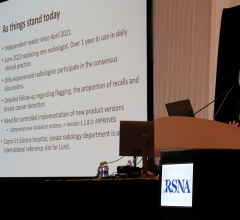

For more information: www.pubs.rsna.org